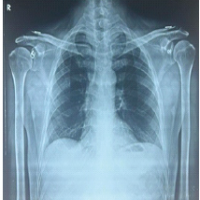

A 22-year-old girl presented with complaints of pain and swelling over her right knee for the past 5 months. The patient also complains of difficulty in squatting. No history of trauma or any other systemic illness. On clinical examination of her right knee, swelling of size 3 × 2 cm is present over the proximal one-third of the anterior aspect of the leg. No local warmth. No signs of inflammation. Tenderness is present over the proximal one-third of the tibia. The range of motion (ROM) of her right knee was 0–80° (further painful). Distal pulses were felt. Sensations were intact. Laboratory tests showed mildly elevated C-reactive protein to 2.1 mg/dL and erythrocyte sedimentation rate of 8. Plain radiograph of the right knee (Fig. 1) showed an eccentric osteolytic epiphysio-metaphyseal lesion of the right proximal tibia with a doubtful breach of the anterior cortex.